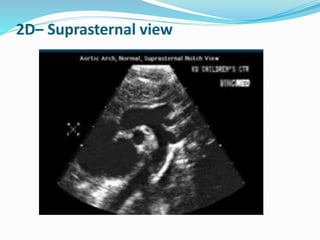

2D– Suprasternal view

Peak transvalvular velocity

 Continuous-wave Doppler ultrasound.

 Multiple acoustic windows

 Apical and suprasternal or right parasternal almost frequently yield

the highest velocity.

 Rarely subcostal or supraclavicular windows may be required.